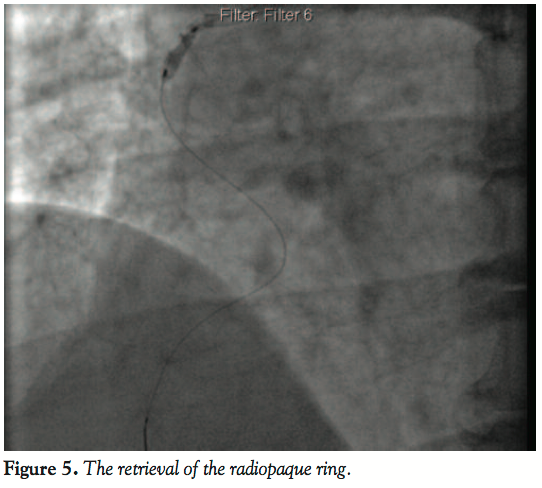

catheter, we noticed that the radiopaque rubber ring, which is attached to the distal end of the guide catheter, was cut off from the catheter (Figure 4). Almost immediately, the same balloon was advanced further beyond the radiopaque ring, inflated to 4 atm to trap the ring, and the whole catheter system was removed through the femoral artery (Figures 5 and 6). The RCA was recannulated and a 3.5 mm x 24 mm Biomatrix stent (Biosensors International) deployed at 16 atm (Figure 7). This was followed by postdilatation of the stented segment with 3.5 mm x 10 mm NC Mercury balloon (Abbott). The procedure was completed successfully without any adverse event. The impending complications related to the remnants of the catheter system were prevented by early recognition of the dehisced radiopaque ring of the guide catheter, which could have caused myocardial infarction, arrhythmias, or sudden death.